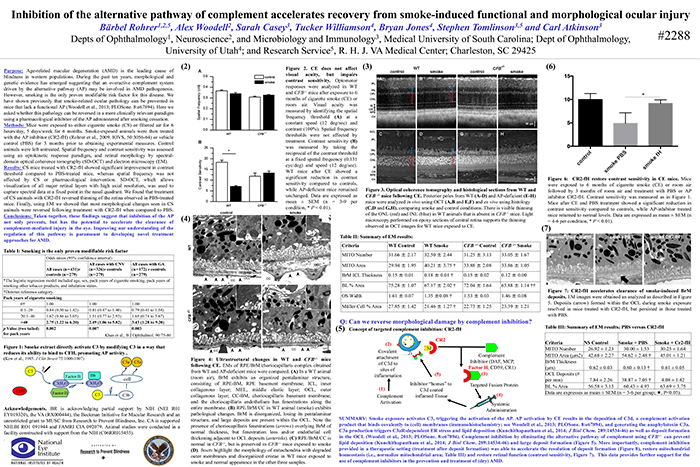

A Targeted Inhibitor Of The Alternative Complement Pathway Accelerates Recovery From Smoke-Induced Ocular Injury

Inhibition Of The Alternative pathway Of Complement Accelerates Recovery From Smoke-Induced Functional And Morphological Ocular Injury

The Alternative Complement Pathway Mediates Functional And Morphological Deficits In A Smoke Model Of Age-Related Macular Degeneration